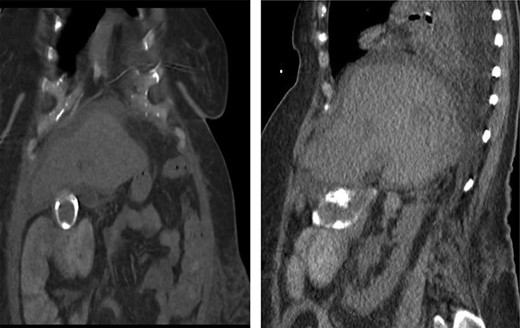

In this study, we were able to track the evolution of the patient’s cholecystoenteric fistulae. She was managed by the same surgeon over the 5 years from her initial episode of cholangitis to her eventual cholecystectomy. The initial CT scan taken during her hospitalization shows an inflamed gallbladder abutting the proximal transverse colon (Fig. 2). The CT enterography obtained 5 years later depicts a fistula that developed in this same region (coronal and sagittal views, Fig. 1). Intraoperatively, the fistula was also found at this location. It is difficult to ascertain when the fistula developed as the patient may have been asymptomatic for years.

CT scan of the same patient during her hospitalization for cholangitis 5 years prior; of note, there is close proximity between the gallbladder and proximal transverse colon; (a) coronal view (b) sagittal view.